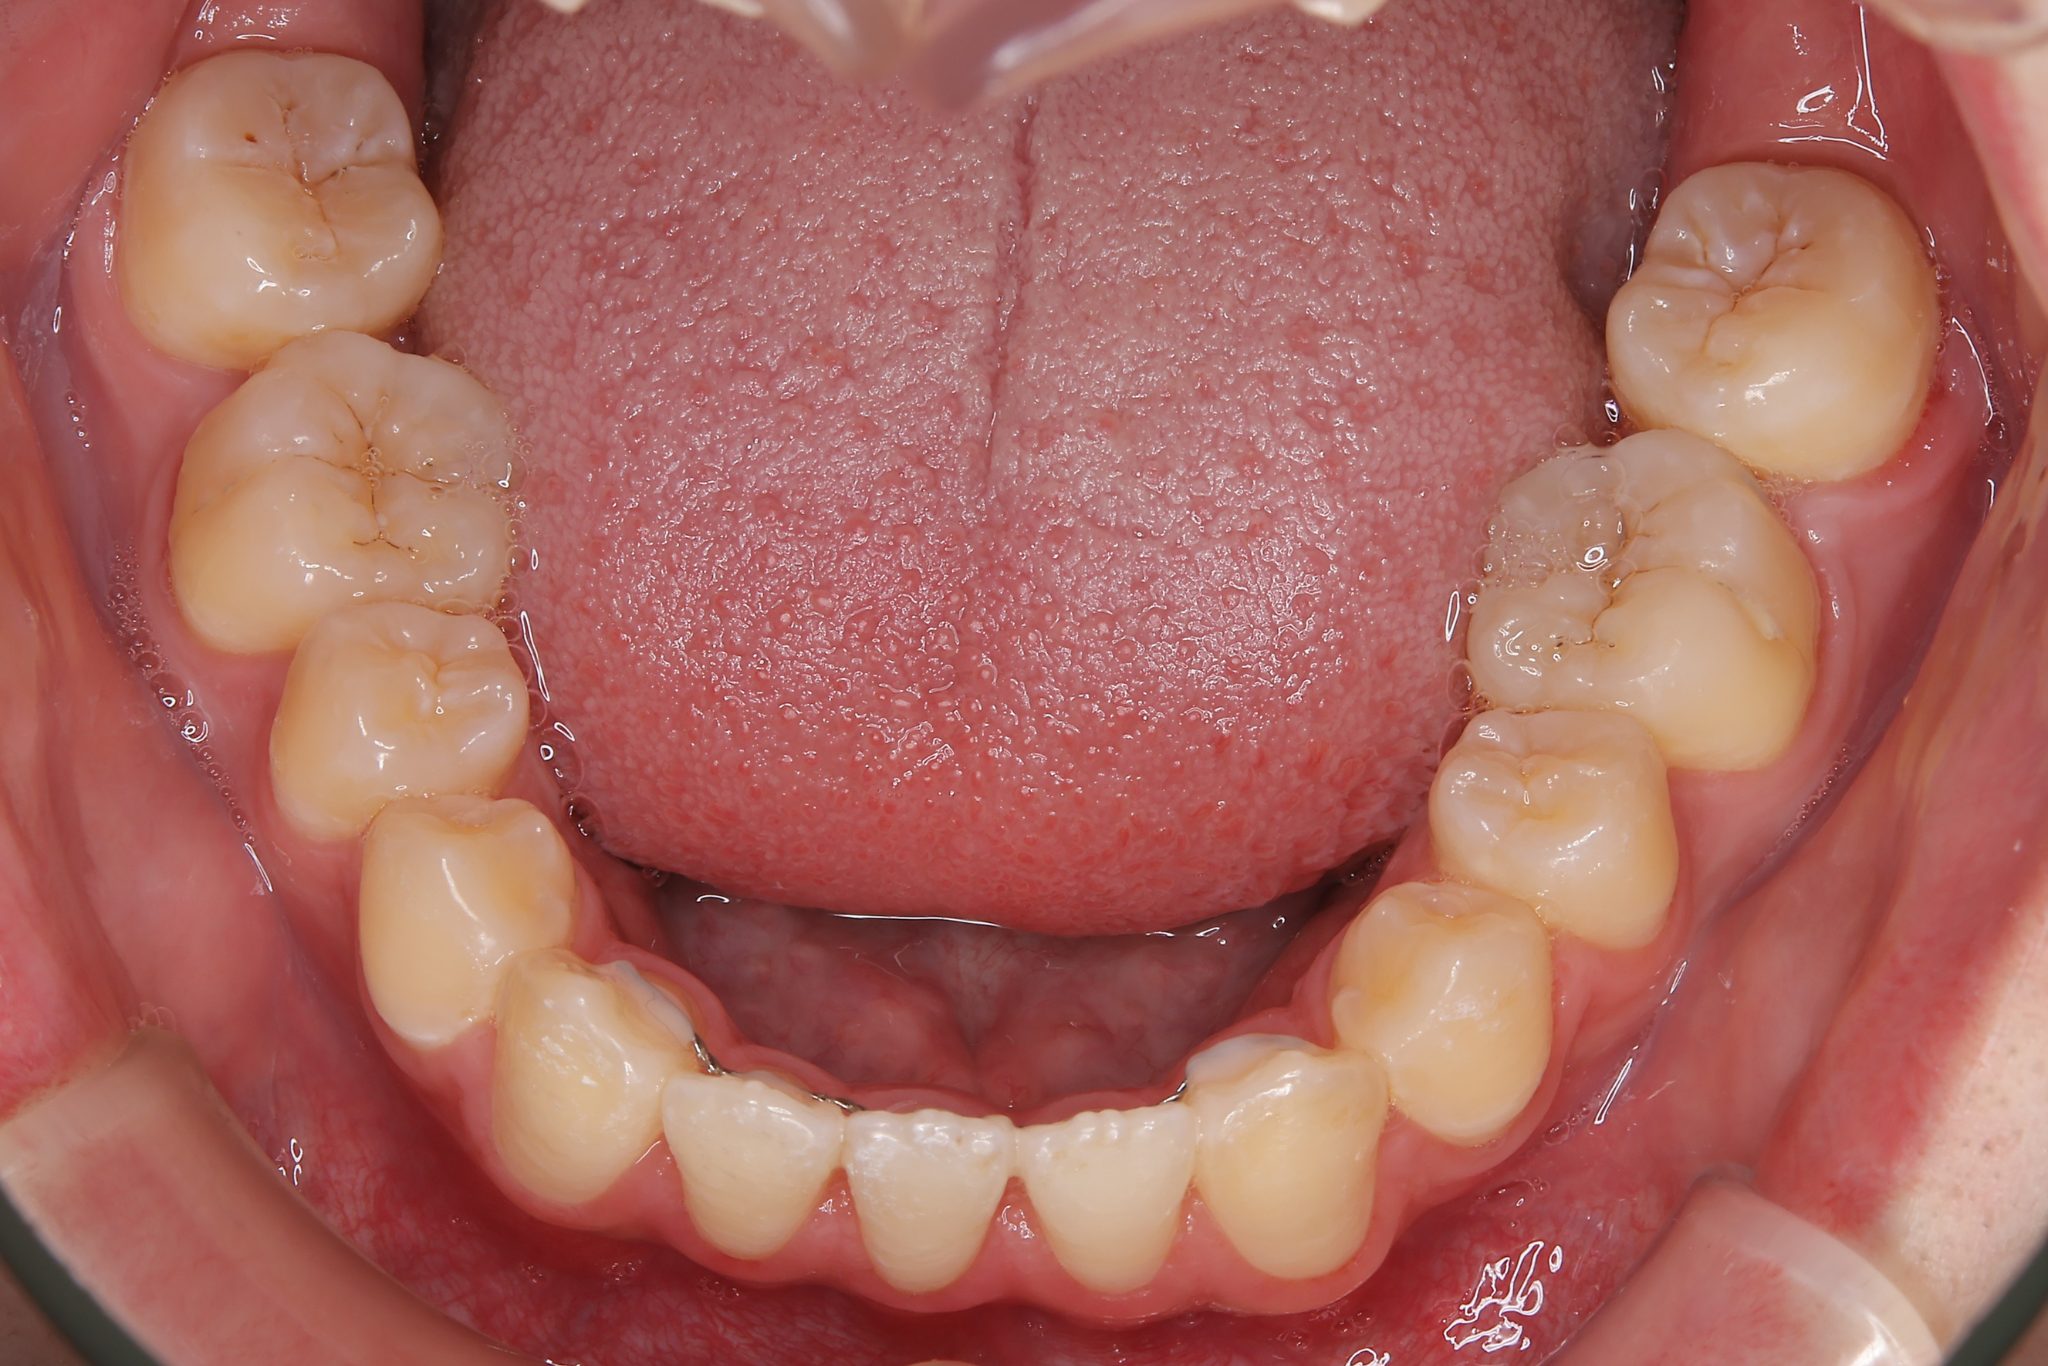

アフター

ワイヤー矯正治療|症例_037

主訴 前歯が少し前に出ている|鼻づまり

施術内容 MSEと下顎リンガルアーチを用いて上下顎骨を拡大した。

その後をマルチブラケット装置を用いて非抜歯で歯牙を配列し、良好な咬合を獲得した。

治癒期間 1年6か月間